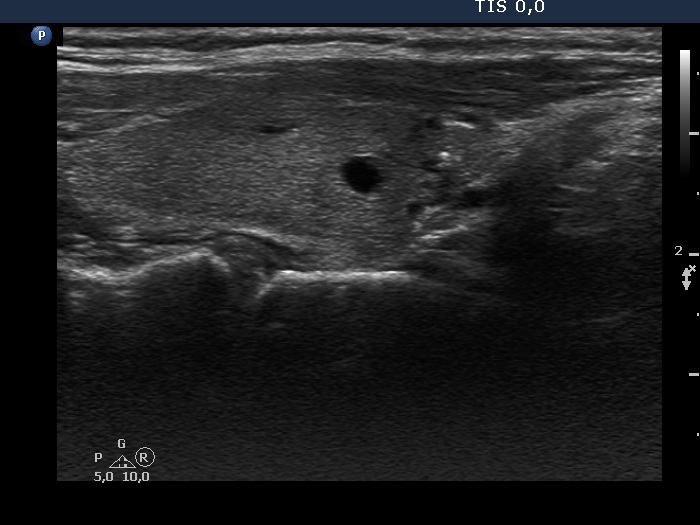

Second examination 9 months after surgery (second row of images):

Clinical presentation: The patient had no complaints.

Palpation: no abnormality.

Ultrasonography: The right and the left lobe remained unchanged except for the appearance of a moderately hypoechogenic lesion in the lower, isthmic part of the right lobe. This lesion contained various hyperechogenic granules and was avascular on Doppler mode. The ultrasound presentation stood for a granulation around surgical thread.